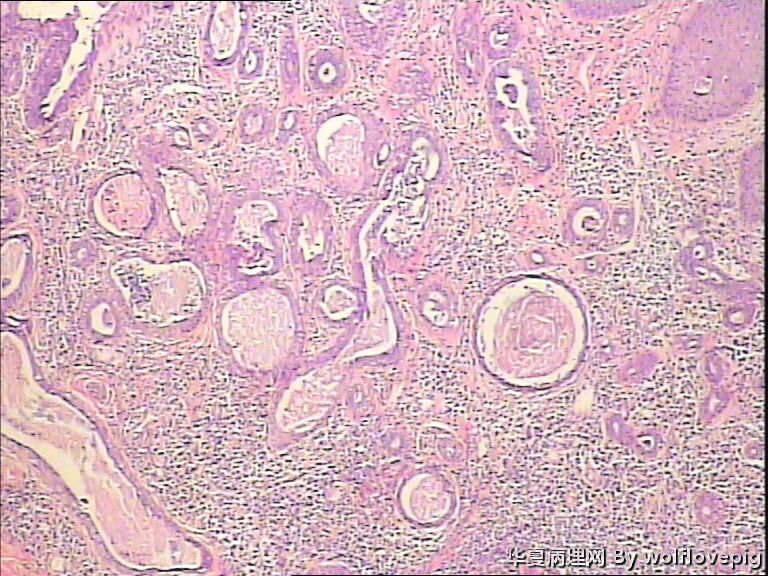

男,38y,腹部皮肤硬节20年。灰白不整形带皮组织一块:3.0*1.5*1.4cm,皮肤表面可见多个小结节样隆起。

图2